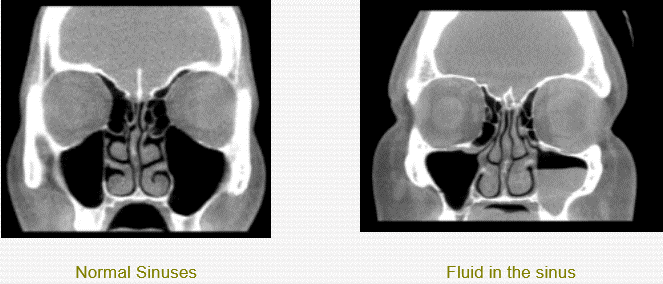

Find relief fast with Texas Allergy Group, your trusted Sinuses Pain Doctor Near Me. Our experienced specialists diagnose and treat sinus infections, chronic sinus pain, allergies, and nasal congestion using advanced, personalized care. We focus on long-term solutions to help you breathe easier and feel better. Book your appointment today for expert sinus treatment near you.